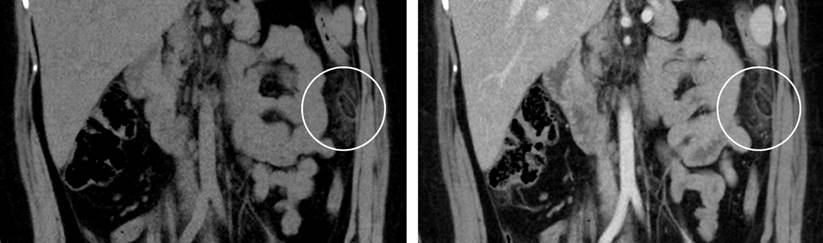

The patient underwent an abdominopelvic computed tomography (CT) with contrast material, which evidenced that the liver, pancreas, spleen, and intestinal loops did not have any significant alteration, the stomach was partially distended with preserved walls and with a hypodense image of the oval fat density of 25 mm x 16 mm that contacts the anterior border of the descending colon, which contains inside a hyperdense image (the sign of the central point) compatible with EA (Figures 1, 2 and 3). She started her medical treatment for pain with diclofenac 75 mg intramuscularly every twelve hours, paracetamol 500 mg orally in only one dose, metronidazole 500 mg orally every eight hours, and simethicone (gaseovet) 15 drops every eight hours. She was indicated to have a soft low-fat diet. The patient was discharged after two days on the following medications: paracetamol 500 mg (10 tablets), tramadol 50 mg (4 tablets), metronidazole 500 mg (9 tablets), and metoclopramide 10 mg (9 tablets).